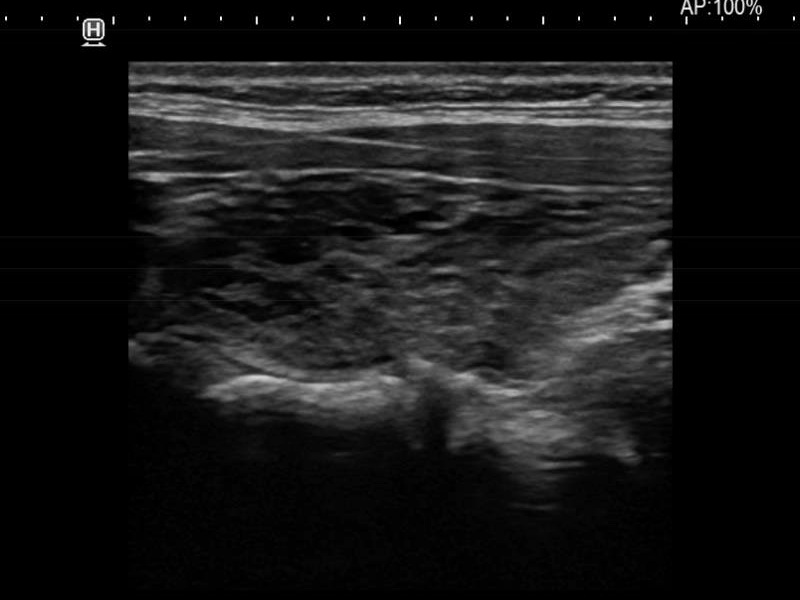

Ultrasonography. The thyroid was moderately hypoechoic and presented with numerous more and less hypoechoic discrete lesions. The largest of the latter was in the lower ventromedial part of the left lobe and had cystic areas and intranodular echogenic figures. The latter included typical comet tail artifacts, back wall cystic figures and some ambiguous small bright granules. The lesion showed both perinodular and intranodular vascularity. Compared with the former examination the nodule increased by 22% in volume. This difference is within the intraobserver variation.

Comment. Based on the presence of typical comet-tail artifacts, the questionable punctate echogenic granules are worth considering also colloid crystals.